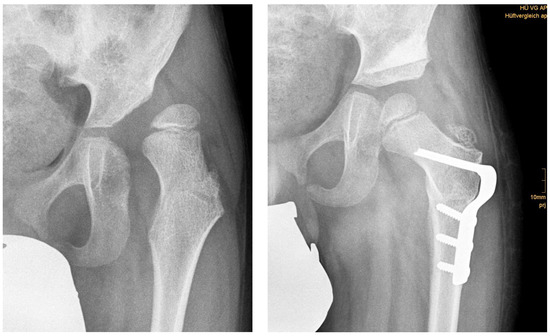

Three months after surgery, children with DDH showed significant decreased RMI compared with children with NDH in a two-sample Student’s t-test (2.77 ± 6.90% vs. 12.94 ± 13.50%; p = 0.011). More often an osteotomy of the iliac bone (Salter innominate, Pemberton, Chiari) was carried out in patients with DDH than with NDH (27 vs. 17; p < 0.001). In cases with combined one step iliac and femoral osteotomy, the residual RMI was significantly lower than in cases with osteotomy of the femur alone (7.02 ± 11.1% vs. 16.85 ± 4.71%; p < 0.001) (Table 4, Figure 1 and Figure 2).

Figure 2.

(left) Anteroposterior radiograph of a nine-year-old male with LCPD; (right): result three months postoperatively.